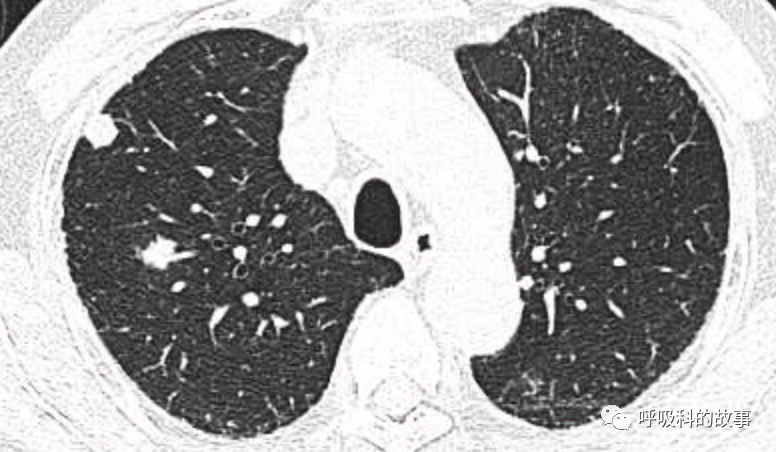

1个月前,我们收治了一个80多岁的男性患者,两肺多发结节和肿块,锁骨上淋巴结也触及肿大,在接诊时我们就预感不妙,患者很可能是患上了肺癌。后来经过穿刺后明确为大细胞神经内分泌癌,CT如下。

图1-11:该患者各个角度的影像图像

(上下滑动查看全部图片)